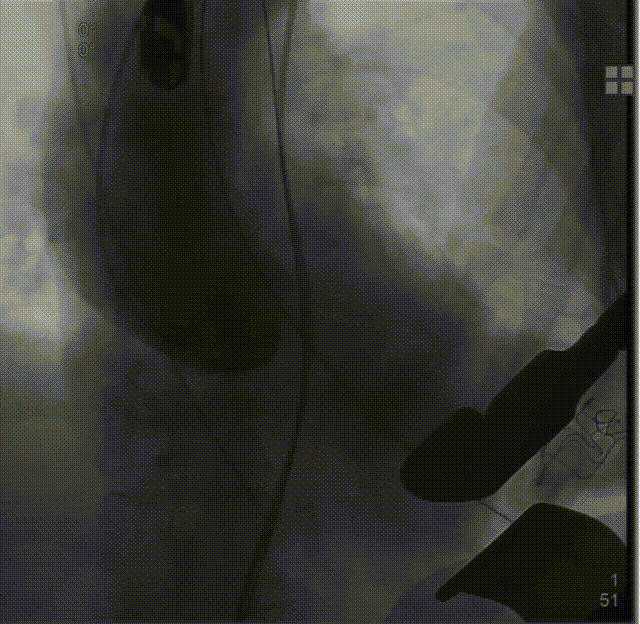

经股动脉送入猪尾导管,行根部造影:

定位件入窦后造影: